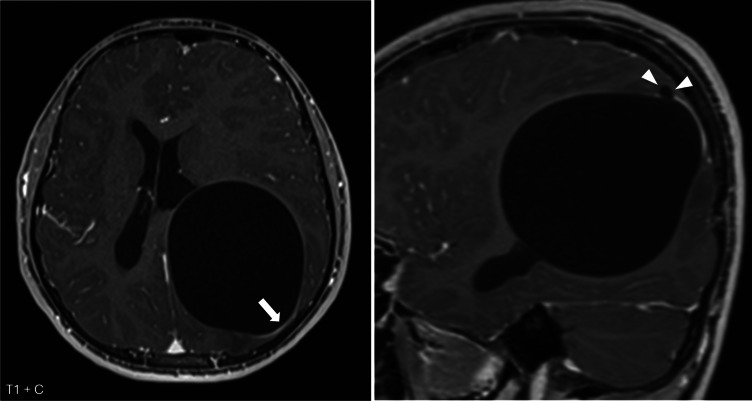

教学要点:当怀疑有脑包虫病时,需要胸腹影像学检查颅内外病变。当发现无并发症的轴内囊肿时,应鉴别诊断包虫病,特别是来自或有流行地区旅行史的患者,或已知接触过狗、羊或牛的患者。胸腹影像可能有助于诊断,因为包虫病更常累及肝脏和肺部,很少累及大脑。

Teaching point: When hydatid disease in the brain is suspected, thoraco-abdominal imaging is warranted to detect extracranial lesions. When an uncomplicated intra-axial cyst is encountered, hydatid disease should be in differential diagnosis, especially in patients from or with travel history to endemic areas, or with known exposure to dogs, sheep or cattle. Thoraco-abdominal imaging may aid diagnosis as hydatid disease more commonly affects the liver and lungs and only rarely the brain.